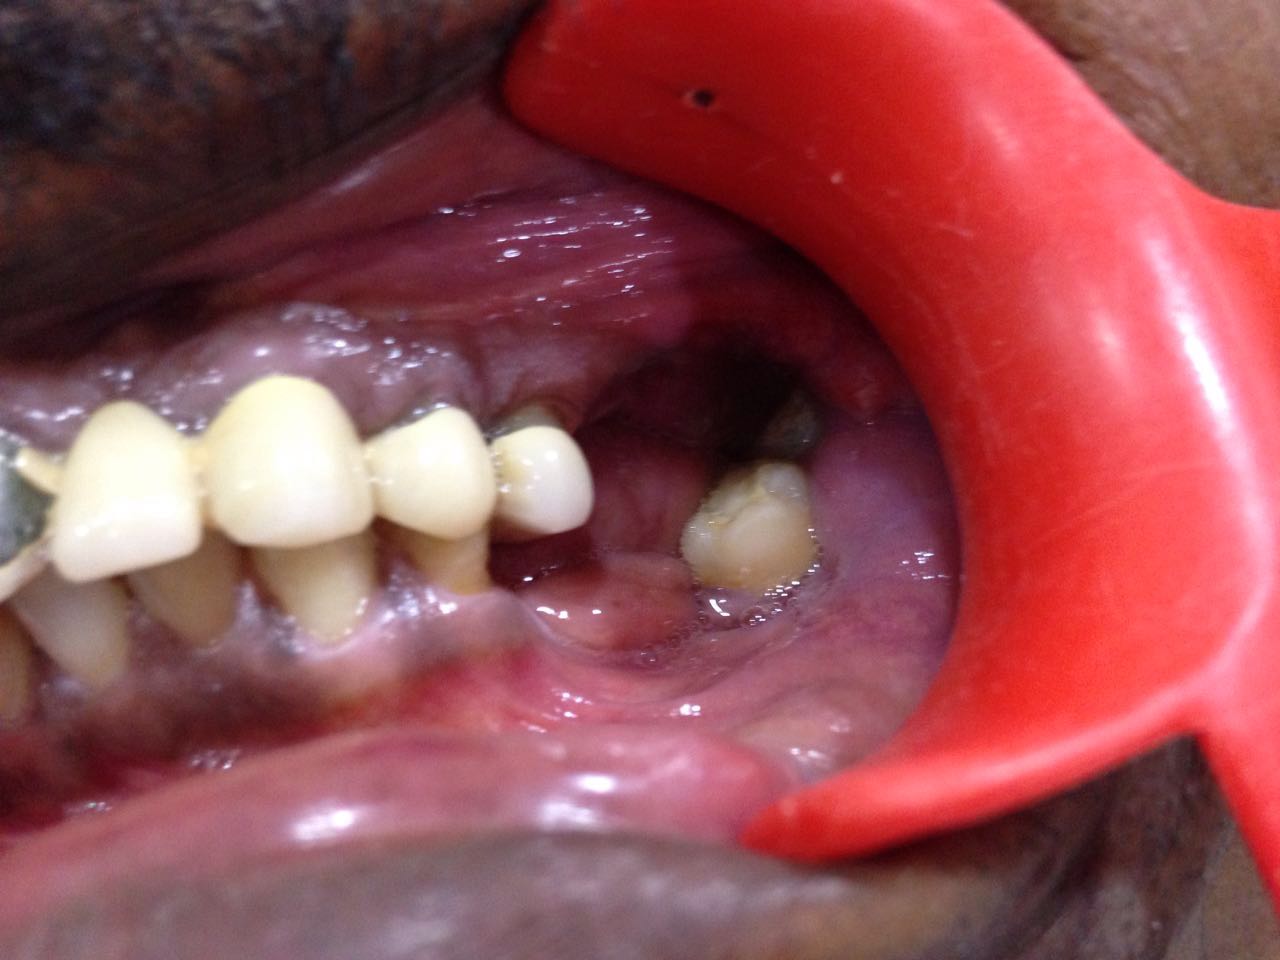

Full Mouth Case

Featured Case Studies